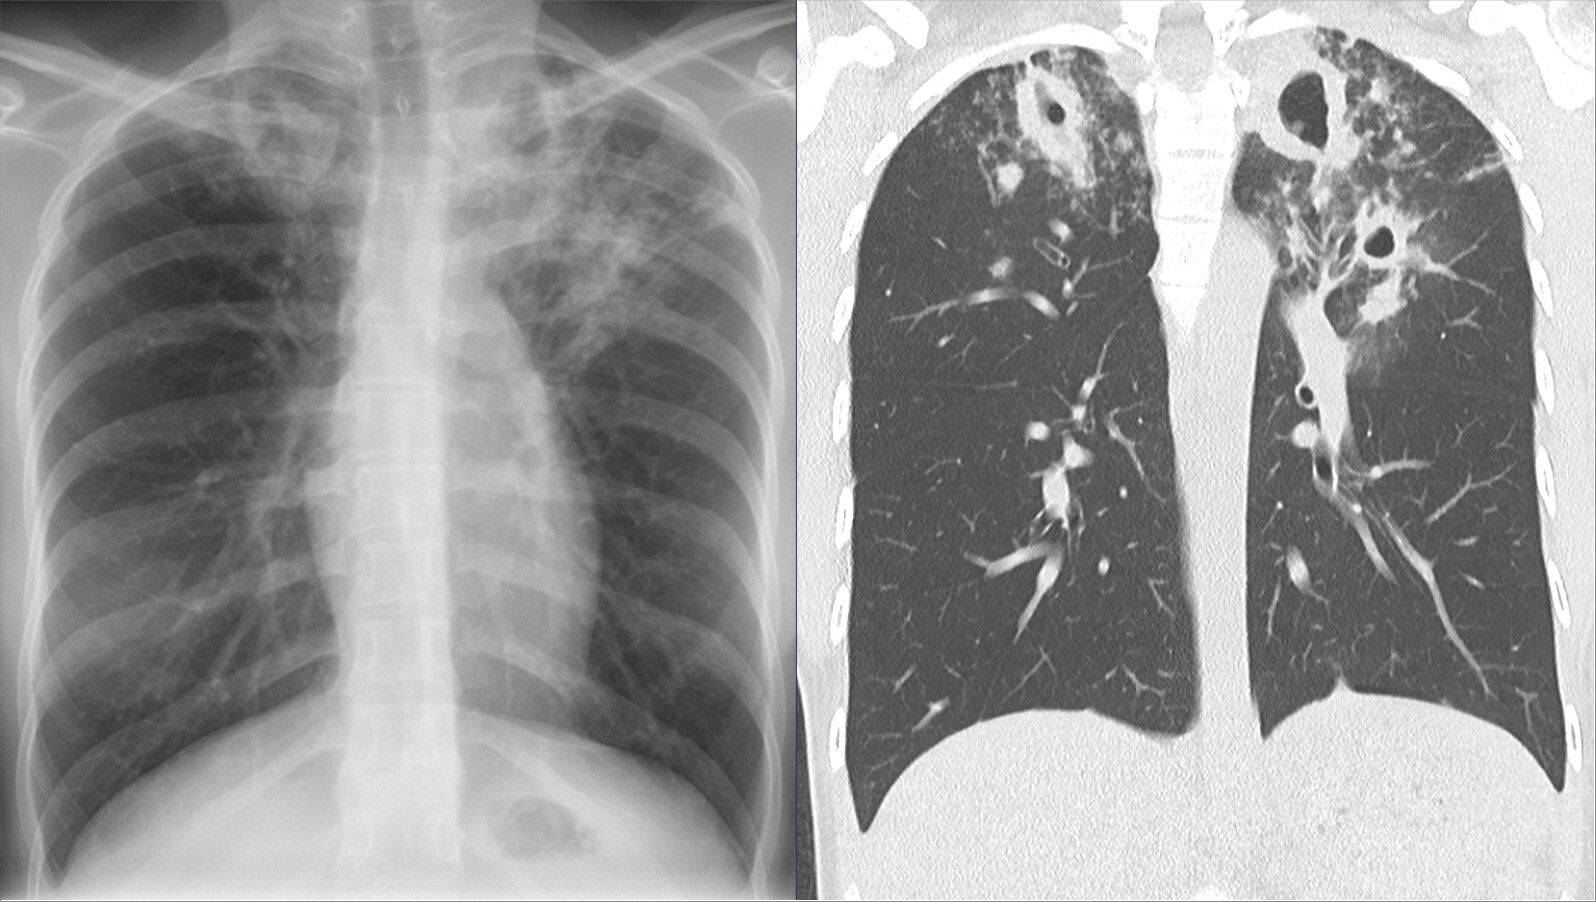

Фото: commons.wikimedia.org, Hellerhoff, Creative Commons Attribution-Share Alike 4.0 International license.